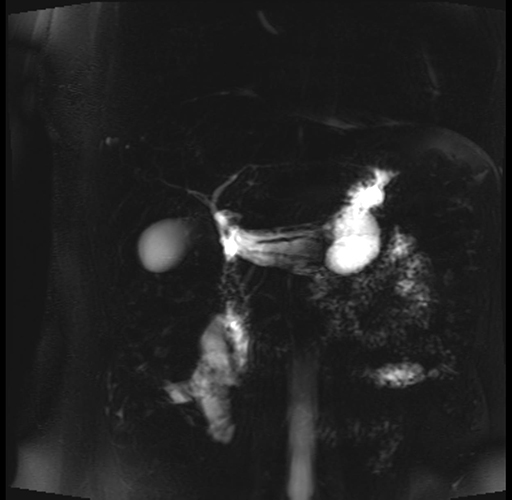

Imaging Analysis

Look through the patient's CT scan to identify any areas of concern for the necessary procedure.

Based on your CT findings, which issue(s) are present and would give reason for "planned slowing down moment(s)" in this case?